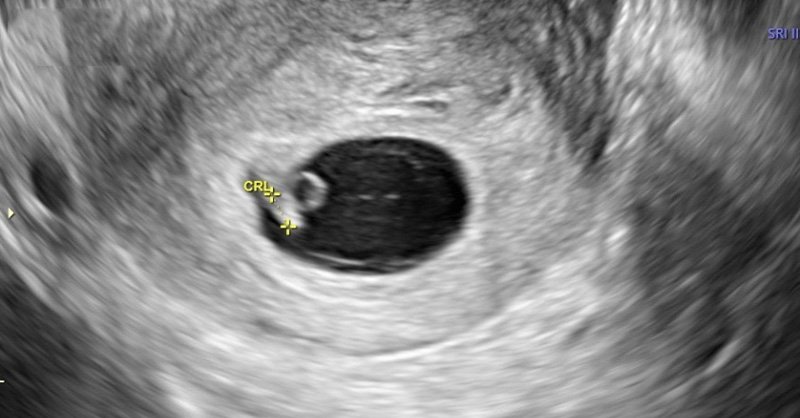

Kiểm tra kết quả

- Xét nghiệm máu hoặc siêu âm sau 14 ngày để xác nhận mang thai.